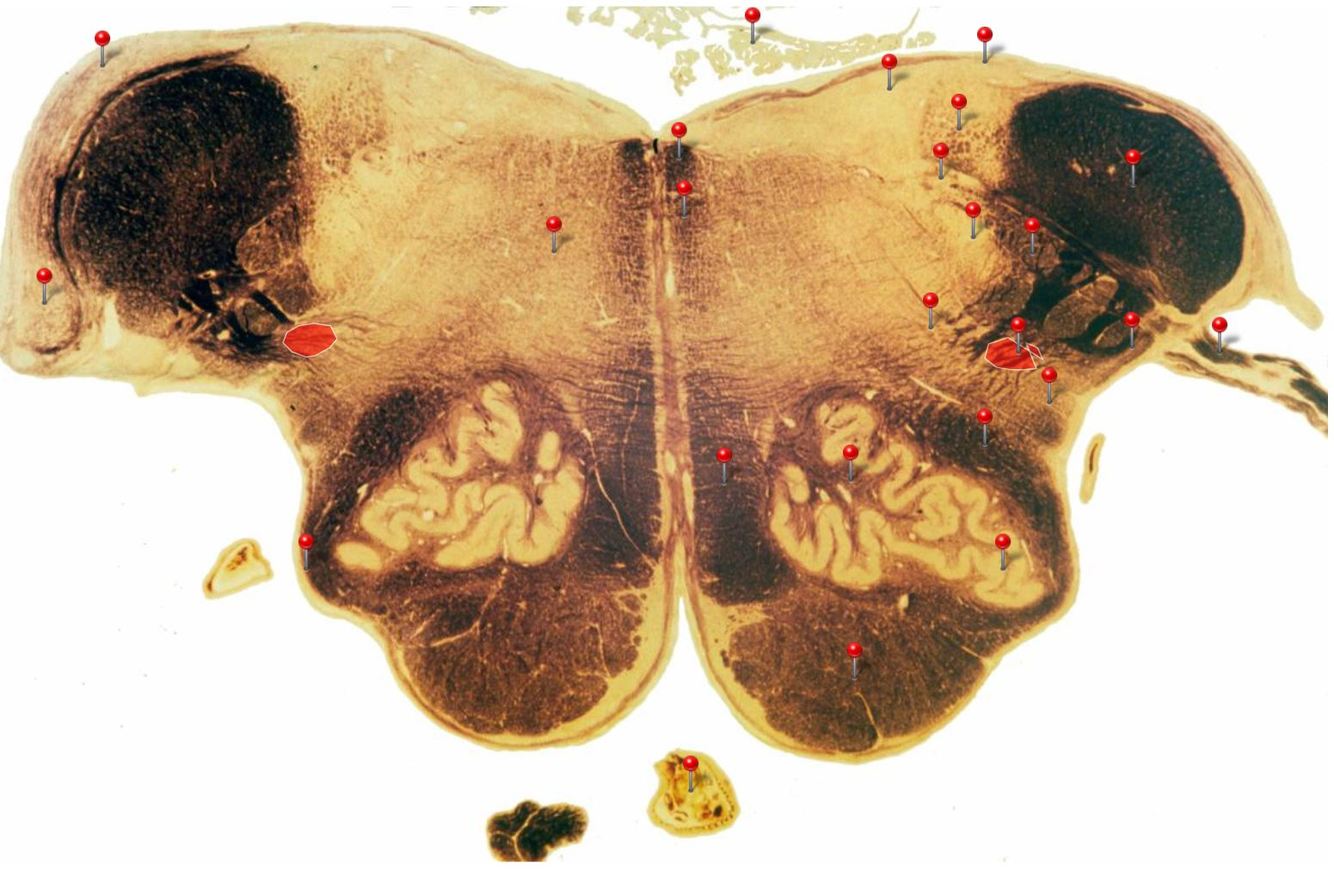

11

Q

A

Corticospinal Tract

Rostral Medulla

Controls precision and speed of skilled movements involving the distal muscles of the contralateral limbs, particularly those of the hands and fingers

12

Nucleus Ambiguus

Neurons supply the muscles of the pharynx, larynx, upper oesophagus and heart

14

Olives

Elevations formed by the inferior olivary nuclei which integrate information from a variety of sources before relaying it to the cerebellum

16

Medial Vestibular Nucleus

Process inputs from vestibular receptors of the inner ear and are involved in the regulation of posture and the coordination of head and eye movements

21

Inferior Olivary Nucleus

Plays an important role in the learning of new motor skills

23

Spinal Trigeminal Nuclei

Processes sensory inputs, particularly pain and temperature, from the head and neck and relays them to the ventral posteromedial nucleus of the thalamus

28

Inferior Cerebellar Peduncle Rostral Medulla Formed by pathways passing in both directions between the medulla and cerebellum

31

Lateral Vestibular Nucleus Rostral Medulla Contains cell bodies of the (lateral) vestibulospinal tract which regulates the activity of **axial** and **proximal** limb muscles in order to **maintain balance and posture**